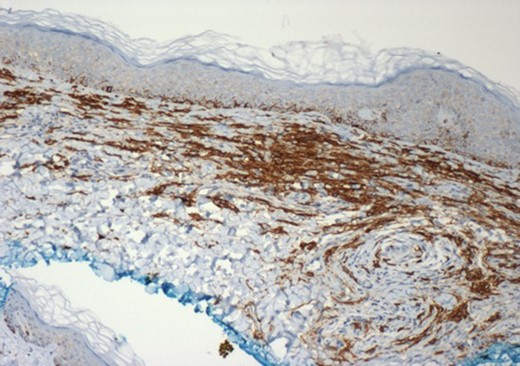

A bone marrow aspirate and trephine biopsy demonstrated a diffuse infiltrate of spindle-shaped MCs (Fig. 2). Investigations for other organ involvement were negative. The patient was diagnosed with SM and started on prophylactic anti-histamine therapy and apart from occasional night sweats, remains well.

Immunoperoxidase CD117 (c-KIT) stained tissue section of a skin biopsy of the left breast. Mast cell cytoplasmic membrane is stained brown (×10 magnification).